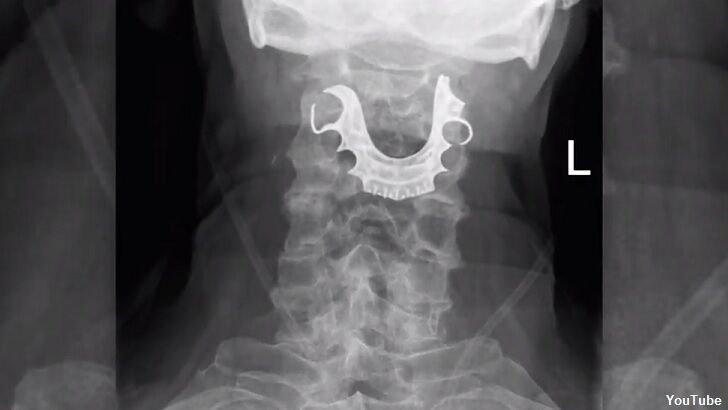

When the medication prescribed by the doctors failed to alleviate the pain and, in fact, the man's ordeal got worse, went back to the emergency room two days later. At that point, doctors peered into the man's throat using an endoscope, which is a flexible tube containing a camera, and spotted "metallic semicircular object." Much to their surprise, when they asked the patient what that could have been, he mentioned that his dentures had gone missing during his surgery a few days earlier.